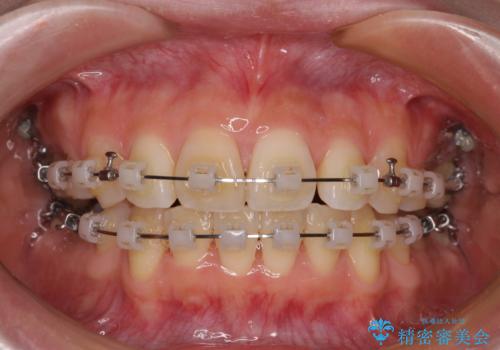

- 矯正装置

- クリアブラケット

- 奥歯の欠損と、抜歯矯正の後戻りを気にして来院された患者様です。

上下前歯をワイヤー保定していましたが、強い舌の突出癖により上下ともにスペースができ、上下前歯は非接触になっていました。

マウスピース矯正でもワイヤー矯正後でも対応可能でしたが、自己管理の煩わしさからワイヤー矯正後を選択されました。

舌のトレーニングをしっかりと行っていただきながらワイヤー装置により矯正治療を行い、途中でインプラントを埋入し、矯正治療後に補綴治療を行うこととしました。